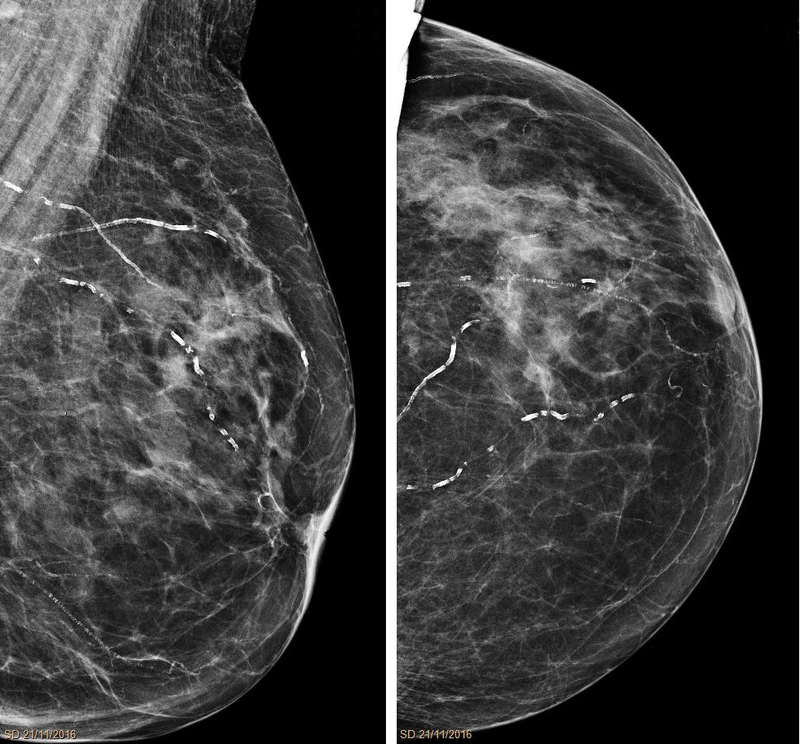

Mönckeberg medial calcific sclerosis results in the calcification of the muscular tunica media portion of medium-sized arteries.

Mönckeberg medial calcific sclerosis is non-obstructive.

Mönckeberg medial calcific sclerosis is typically not clinically significantly.

Mönckeberg medial calcific sclerosis is usually an unintended discovery in X-ray mammography.